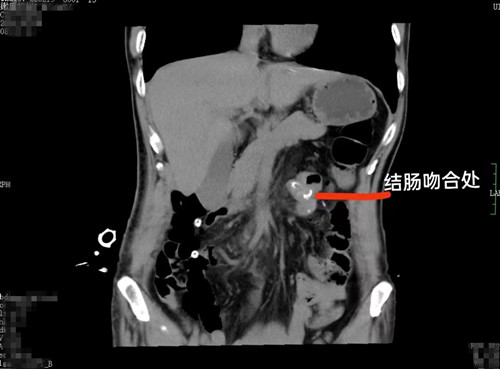

68岁的李爷爷平素身体硬朗,前些日子感觉小腹隐痛,到捷克论坛 检查患上了泌尿系结石,遂准备在捷克论坛 泌尿外科进行手术碎石。没想到术前详细检查时,发现横结肠肿瘤性病变,最终确诊结肠癌,接受了手术治疗。

在泌尿四病区和普外三病区的联手下,李爷爷先接受了钬激光碎石手术,又接受了腹腔镜下右半结肠癌根治术。看到术后病理结果,李爷爷终于相信自己是患了结肠癌,心理防线彻底被击垮,开始抗拒治疗,闹着要拔管出院。